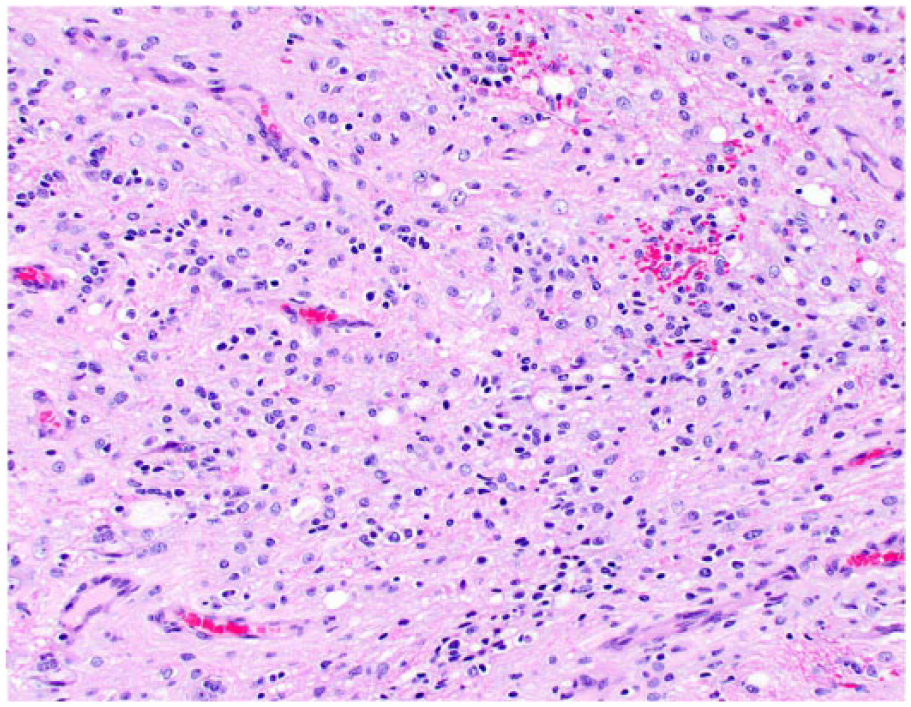

Histologically, all tumors were poorly demarcated, often infiltrative, and affected mainly the spinal gray matter. Oligodendrogliomas (cases 1, 3, 6, and 7) were poorly demarcated and affected primarily the gray matter, but also extended into the adjacent white matter (Fig. 2). Neoplastic cells were arranged in sheets or cords supported by preexisting parenchyma or a fine fibrovascular stroma with occasional microvascular clusters (glomeruloid vessels; cases 3 and 6). Neoplastic cells were mildly to moderately pleomorphic and had a moderate amount of cytoplasm, with distinct borders, that was either clear (forming a perinuclear halo) or contained basophilic, fibrillar, mucinous material. Nuclei were round-to-oval and had finely stippled to dense chromatin and 1–4 nucleoli. Overall mitotic activity was absent or low. Small areas of necrosis and hemorrhage were present in all 4 tumors. Case 6 was highly cellular and had increased cellular pleomorphism, with extensive areas of necrosis (Fig. 3) and 19 mitoses in ten 400× fields. Cases of gliomatosis cerebri (cases 4 and 5) were characterized by extensive, segmental, unilateral infiltration of neoplastic glial cells throughout the dorsal, lateral, and ventral funiculi and ventral horn of the spinal cord with no discrete mass formation (Fig. 4). There was a lack of distinction between the white and gray matter in the affected areas. Neoplastic cells were supported by preexisting neural tissue or small numbers of capillaries and had a moderate amount of round-to-polygonal, eosinophilic, vacuolated cytoplasm with indistinct borders. Nuclei were round-to-oval and had finely stippled chromatin with indistinct nucleoli. Mitotic index was 7 (case 4) and 11 (case 5) in ten 400× fields. Areas of hemorrhage or small perivascular accumulations of lymphocytes and plasma cells were observed occasionally. The astrocytoma (case 2) was poorly demarcated and affected both gray and white matter, although it appeared to arise primarily from the gray matter (Fig. 5). Neoplastic cells were widespread throughout the affected areas and were supported by preexisting neural tissue. These cells had moderate pleomorphism and scant, round-to-polygonal, eosinophilic cytoplasm with distinct borders. Nuclei were round to slightly elongate and had densely coarse chromatin with indistinct nucleoli. Mitoses were absent. IHC findings are summarized in Table 2 and shown in Figures 6–9. The main features of canine glial tumors of the spinal cord reported in the veterinary literature are summarized in Supplemental Table 1 (available at http://vdi.sagepub.com/content/by/supplemental-data).

Spinal oligodendroglioma in dog 3. Sheets of neoplastic cells admixed with mucinous material or a perinuclear clear halo efface the gray matter. H&E.